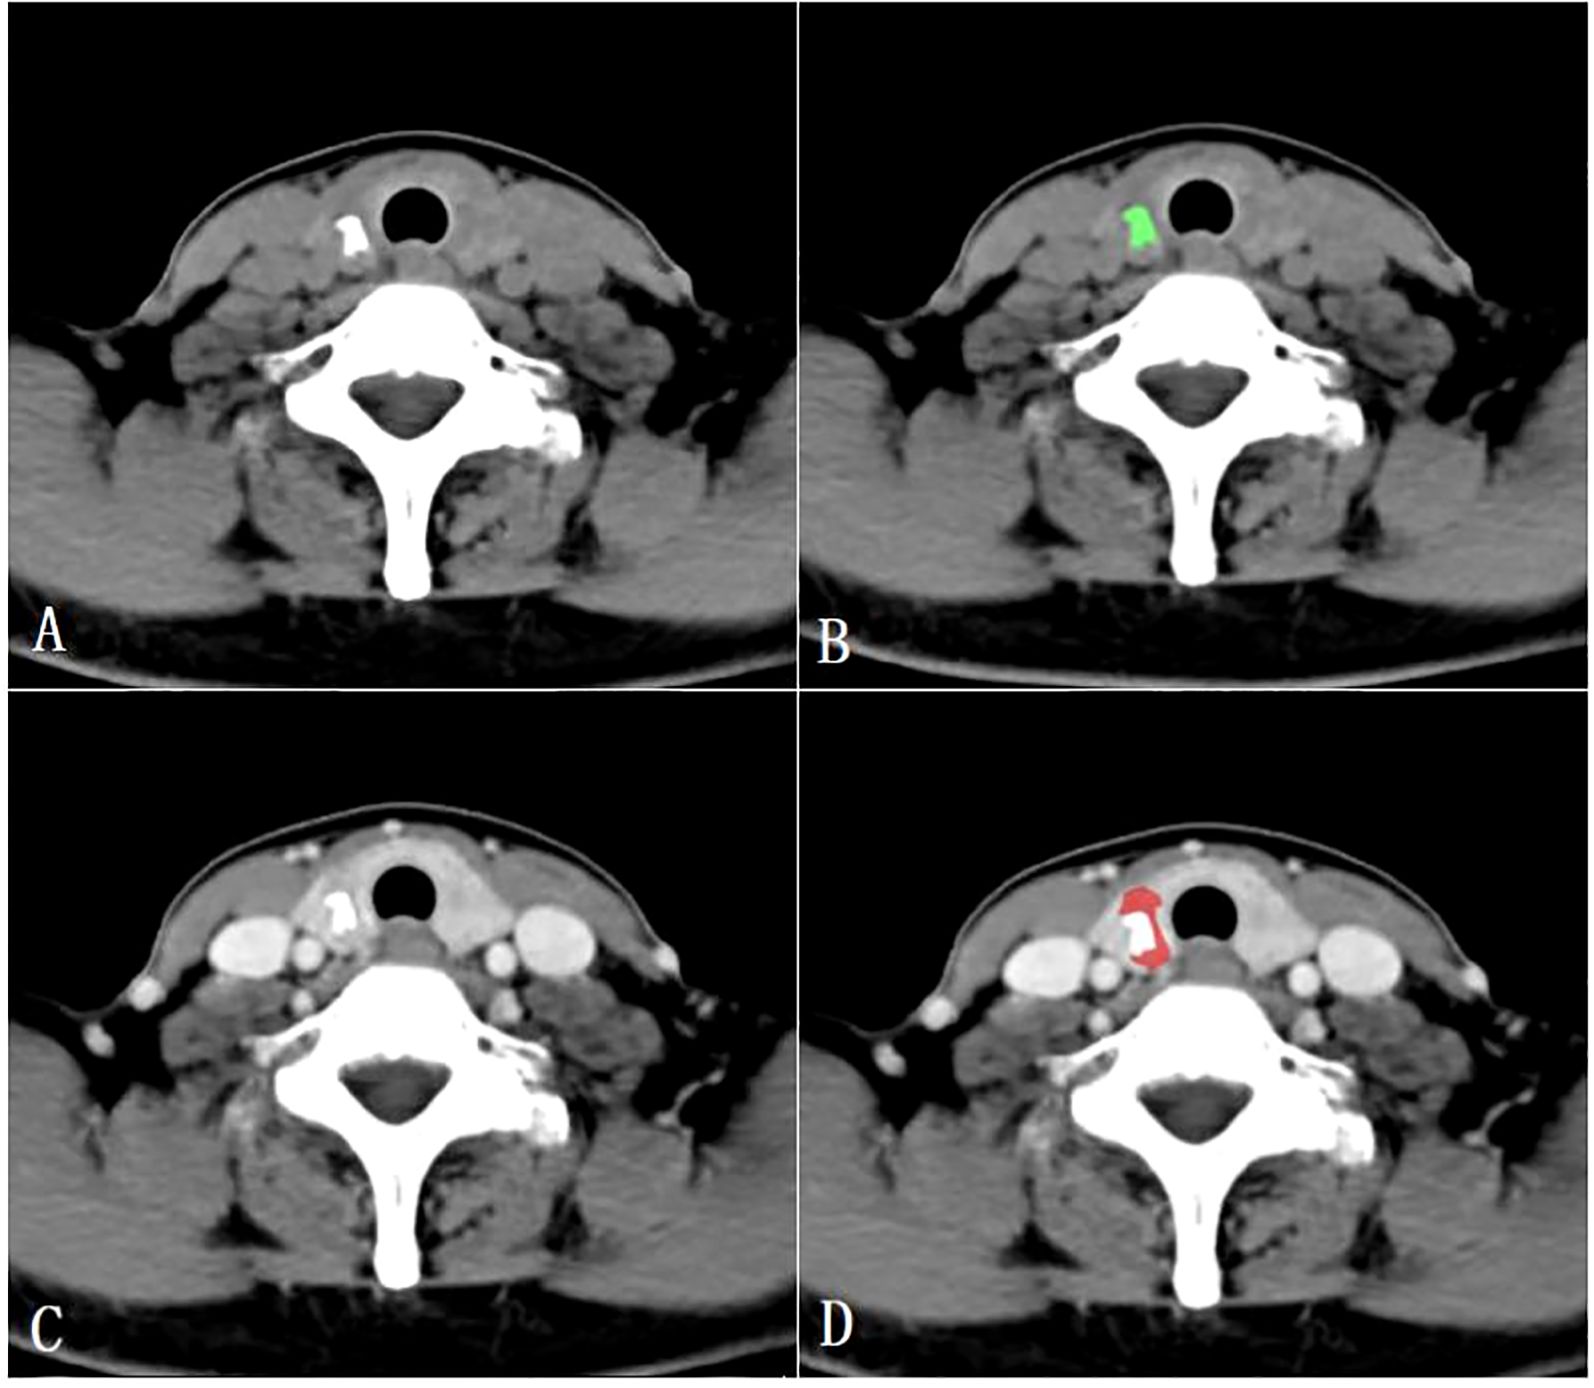

All CT images were retrospectively analyzed and evaluated using the picture archiving and communication systems (PACS) by two radiologists with 15 years (radiologist #1) and 8 years (radiologist #2) of expertise in diagnosing thyroid disease. Subsequently, the images were imported into the MaZda software (version 4.6, Instytut Elektroniki, Technical University of Lodz, Poland) (15) for further analysis. The two radiologists reached a consensus and manually outlined the margins of the parenchymal area on the maximum central level of the tumor, as well as the calcified area on the maximum calcified level of the tumor to define the ROIs. To ensure accurate delineation and to minimize the influence of the interference of CT contrast agents on calcification and calcified artifacts in the parenchymal area, the ROIs for the calcified areas were outlined on unenhanced CT scan images, while the ROIs for the parenchymal areas were outlined on enhanced venous phase CT images (Figure 2).

Figure 2. Region of interest placement in the calcified area of the papillary thyroid carcinoma on unenhanced CT images (A, B); Region of interest placement in the parenchymal area of the papillary thyroid carcinoma on venous phase CT images (C, D).